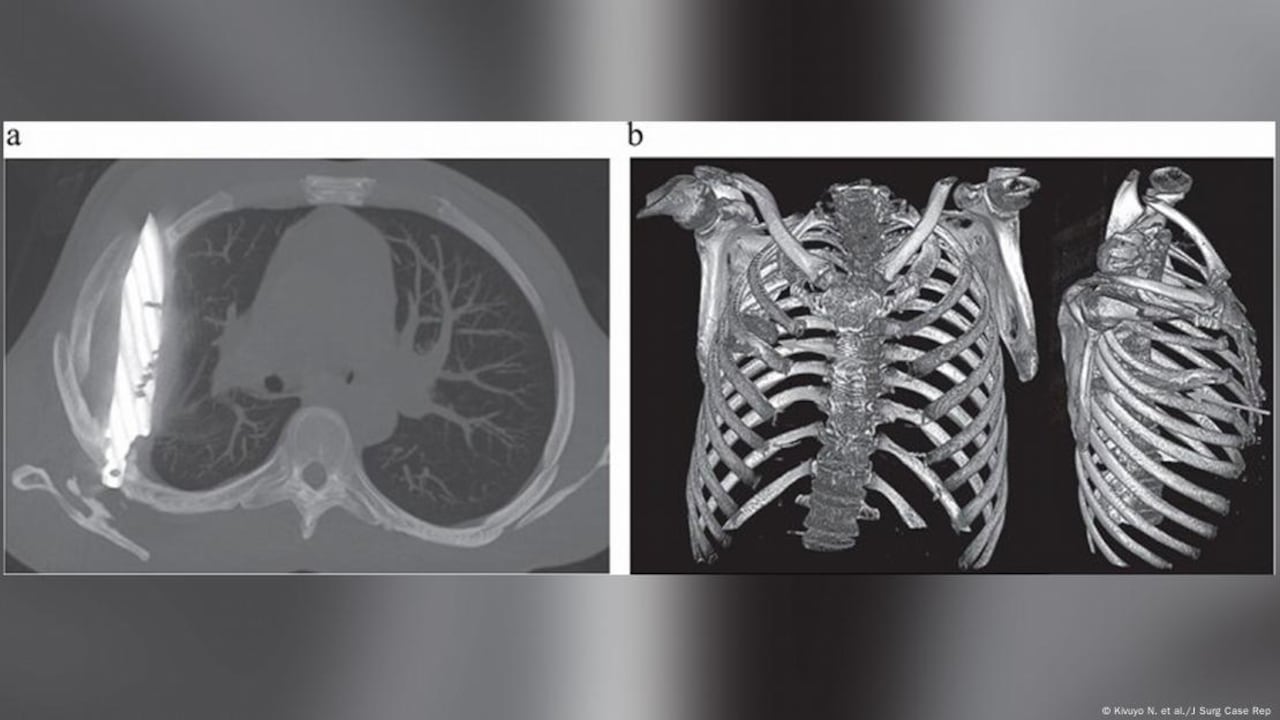

La radiografía realizada actualmente reveló un “objeto metálico retenido” dentro del tórax, pues una tomografía confirmó que se trataba de una hoja de cuchillo completa, incrustada desde la espalda hasta la parte frontal del pecho, rodeada de pus y tejido dañado.

El equipo médico decidió realizar una toracotomía para retirar la hoja, limpiar la cavidad torácica, extraer el pus y colocar un drenaje, el hombre recibió antibióticos de amplio espectro durante una semana.